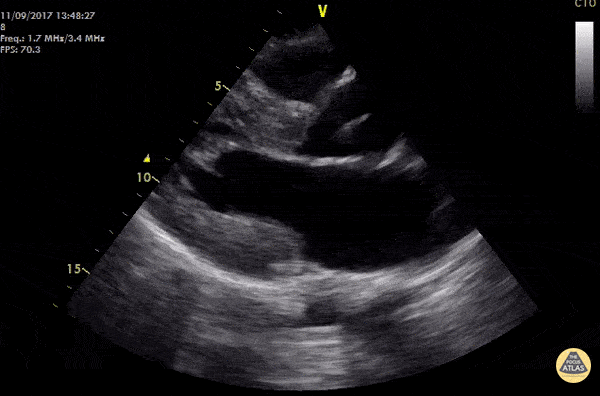

WCUME 2017 Submission for "Creative Caption" - "Uncle SAM" 19 year old male out of hospital cardiac arrest s/p ROSC. POCUS shows hypertrophic interventricular septum with systolic anterior motion of the mitral valve (SAM) causing LVOT obstruction. LVOT gradient was measured at 118 mmHg and AICD was fitted during hospital stay. Treatment for HCM usually recommended if: SAM lesion visualized, IVS >18mmm, LVOT gradient > 30mmHg. Cian McDermott, MD